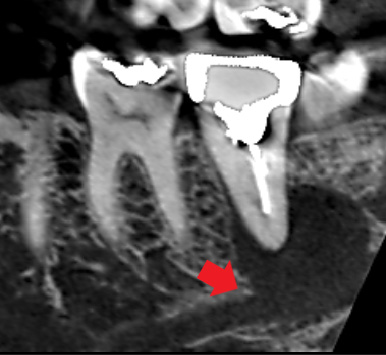

初診時のCT画像では、根の先に大きな膿の影がみられました。

下顎管という下あごの中に通っている太い神経達するほど大きい膿です。再根管治療を行い、根管の中の感染を徹底的に除去しました。